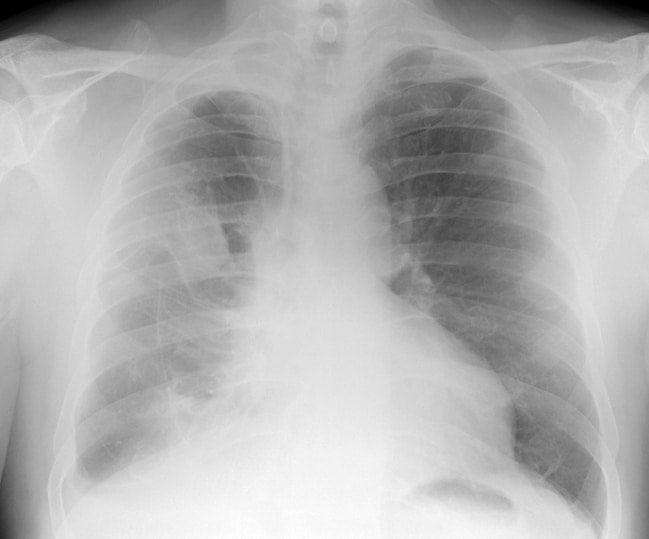

A chest X-ray is a common method of diagnosing asbestos-related disease. Expert physicians certified by NIOSH (National Institute for Occupational Safety and Health) read chest X-rays and determine the existence and level of lung disease related to asbestos exposure. These special X-ray reports are called “B-reads.” A positive B-read is an indication of asbestos-related disease. For cancer, a biopsy and resulting pathology or cytology report are also needed.

2. Chest x-ray with positive B-read (showing bilateral asbestosis or pleural disease),

We will need your help to create an accurate work history timeline. We may ask you to provide the names of co-workers at one or more of your work locations. We will need a recent chest x-ray. And you may need to be examined by a doctor willing to write a causation letter linking your exposure to your injury. If you have qualifying work history and proof of injury, we will ask you to sign affidavits documenting your exposure. When/if you are offered money, you will sign releases to settle your claims. Our asbestos lawyers may also ask you to complete a family survey and provide a copy of a simple will.